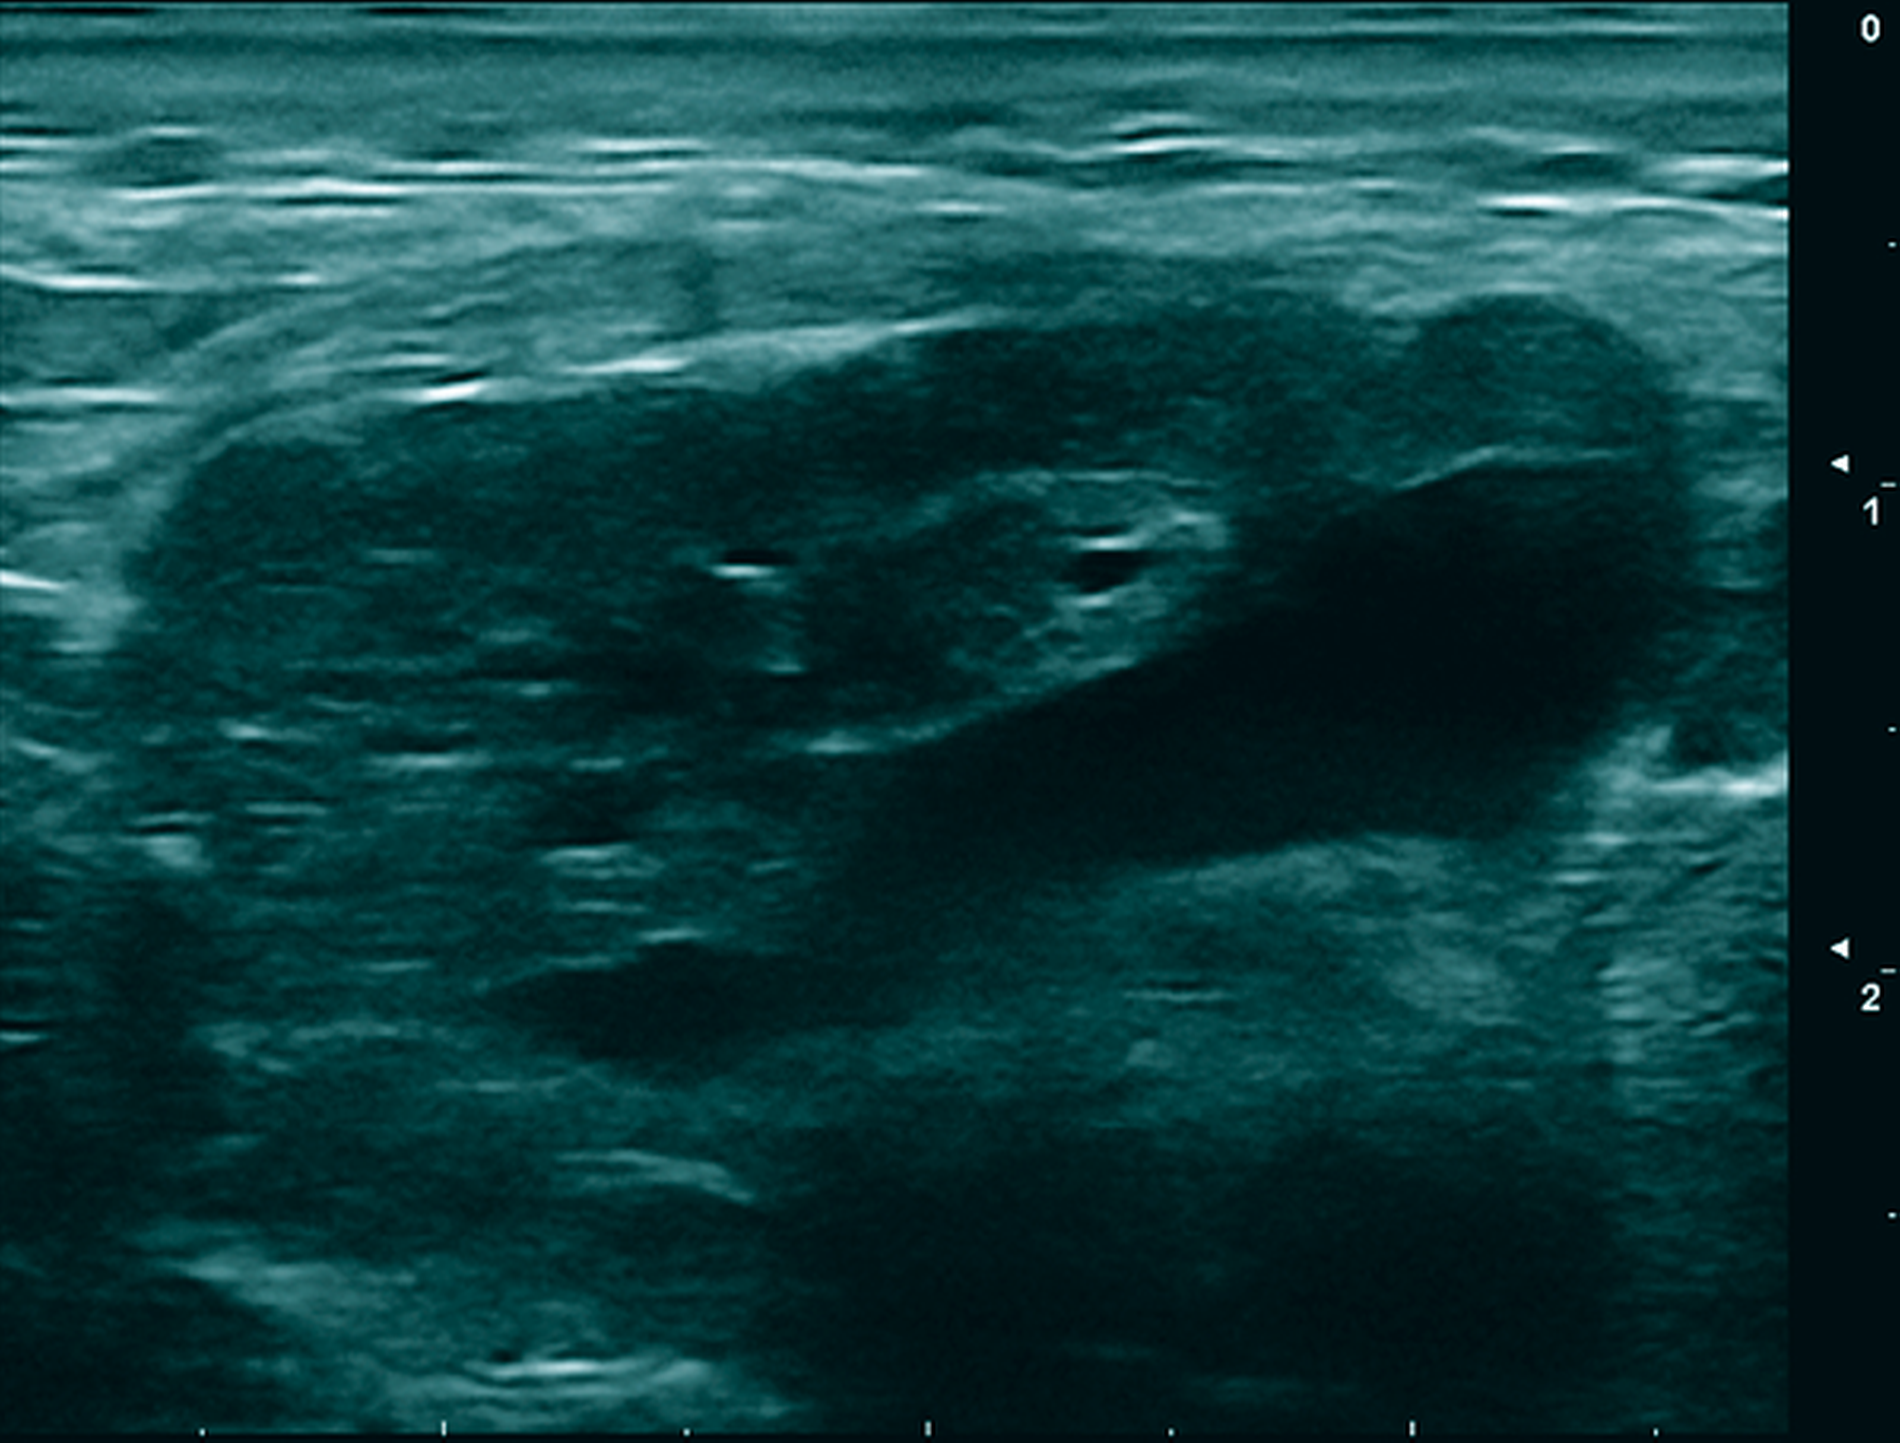

Bei weiter vorliegender Schwellung bei unklarer Ursache erfolgte die Vorstellung des Patienten in der Ambulanz der Universitätsmedizin Mainz. Nach der ausführlichen klinischen Untersuchung des Befunds wurde eine Sonografie durchgeführt. Dort zeigte sich eine ovoide Raumforderung inhomogener Echogenität mit zentral hypo- und peripher isoechogenen Bereichen (Abbildung 2).

Das mittlere Alter bei Erstdiagnose eines SFT liegt bei 60 Jahren, obwohl Fälle in einer Spanne von 14 bis 67 Jahren beschrieben wurden. Männer und Frauen sind gleich häufig betroffen; es liegen keine gesicherten Risikofaktoren für die Entwicklung eines SFT vor. Da es sich bei den klinischen Charakteristika um unspezifische Symptome handelt, spielen bildgebende Maßnahmen ebenso wie die histopathologische Untersuchung eine große Rolle [Kalla, 2018; Schütte et al., 2019; de Morais et al., 2020]. In der Sonografie stellt sich der SFT typischerweise als klar umschriebene, hypoechogene Raumforderung mit variabler Vaskularisation oder aber als heterogene oder polyzyklische Masse dar. Die heterogene Struktur des Befunds kann auf nekrotische, hämorrhagische oder zystische Anteile hindeuten [Jiang et al., 2019]. In der Schichtbildgebung zeigt sich der SFT sowohl in der Computer- als auch in der Magnetresonanztomografie isodens/idointens zur Muskulatur und mit einem heterogenen Kontrastmittelverhalten [Satomi et al., 2014; Kalla, 2018].